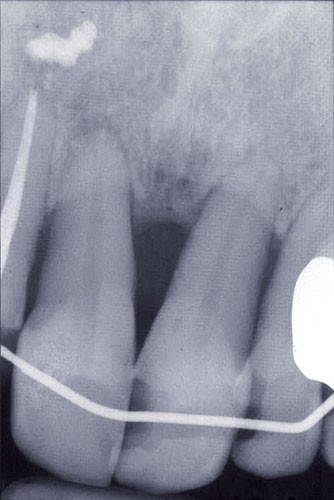

Les examens cliniques et radiographiques montrent une parodontite chronique généralisée (fig. 1a à m).